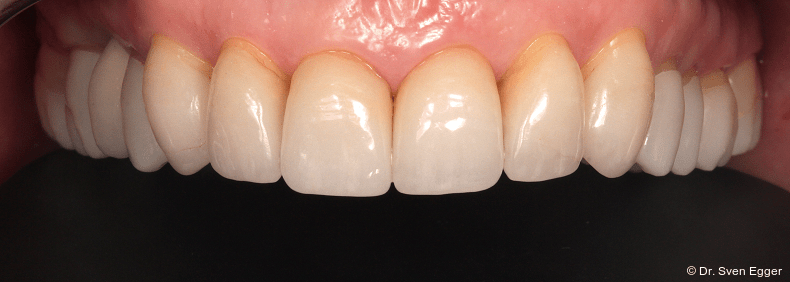

Weiße Ästhetik

- Zahnlänge: Die Verlängerung der gesamten Oberkieferfront um ca. 1 mm empfindet die Patientin als sehr attraktiv, das entspannte Lächeln zeigt fast die gesamte Frontzahnreihe. Der Schneidekantenverlauf folgt der Konkavität der Unterlippe.

- Zahnform: Die größeren und längeren Schneide- und Eckzähne sowie die kleine Stellungskorrektur der beiden seitlichen Schneidezähne fügen sich harmonisch in das Gesamtbild der Restbezahnung ein und schenken der Patientin ein attraktives Erscheinungsbild (Abb. 15).

- Form und Größe, Charakterisierung durch den ausführenden Zahntechniker (Transparenz, Transluzenz) sowie die Oberflächenstruktur (Textur) der keramischen Veneers zeigen ein ansprechendes Erscheinungsbild. Das Längen-Breiten-Verhältnis beträgt nun circa 80 Prozent (Länge 11 mm, Breite 8 mm).

- Zahnstellung: Die leicht nach distal rotierten seitlichen Schneidezähne konnten durch die Einzelzahnrestaurationen etwas ausgeglichen werden. Durch die „Verlängerung“ der Eckzähne konnte gezielt eine gute Front-Eckzahn-Führung in die Veneerrestaurationen eingearbeitet werden.

- Zahnfarbe: Die Zahnfarbe entpricht ganz den Vorstellungen der Patientin (A2, VITA).

Zusammenfassung der ästhetischen Problematik: Es zeigt sich nun hinsichtlich der Länge (Lächeln), Form, Farbe, Stellung der Zähne sowie der rosa Ästhetik ein ansprechendes dentogingivales Erscheinungsbild. Die unteren Frontzähne haben leichten Kontakt auf den Palatinalflächen der oberen Eck- und Schneidezähne. Der Overbite beträgt 4 mm. Der Overjet 2 mm (Abb. 16+17).